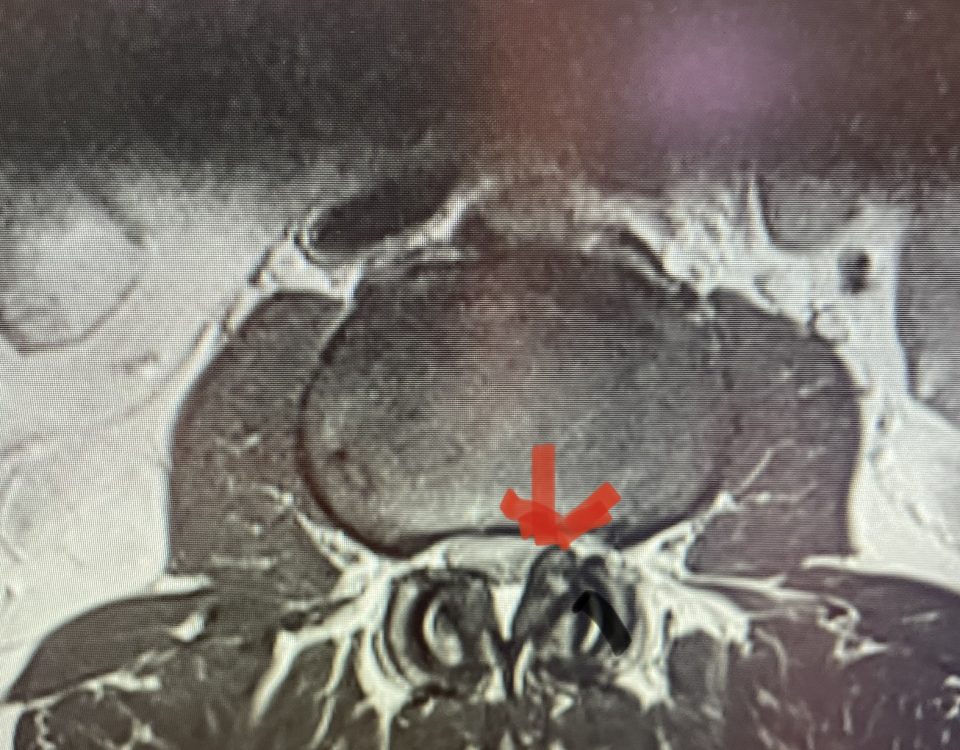

Nervous tissue is soft. The thecal sac is surrounded by a rigid bony ring which forms the spinal canal. Any mass that fills the very small […]